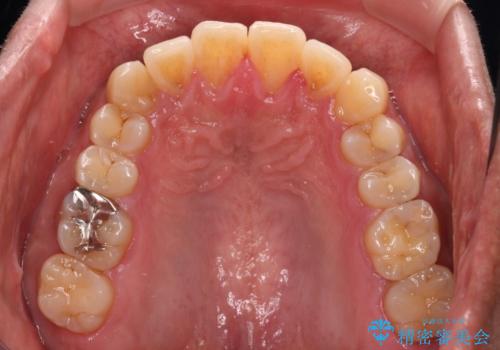

配属異動や長時間勤務などによりインビザラインが十分に装着できない期間があり、インビザライン有効期限5年間ギリギリとなってしまいました。